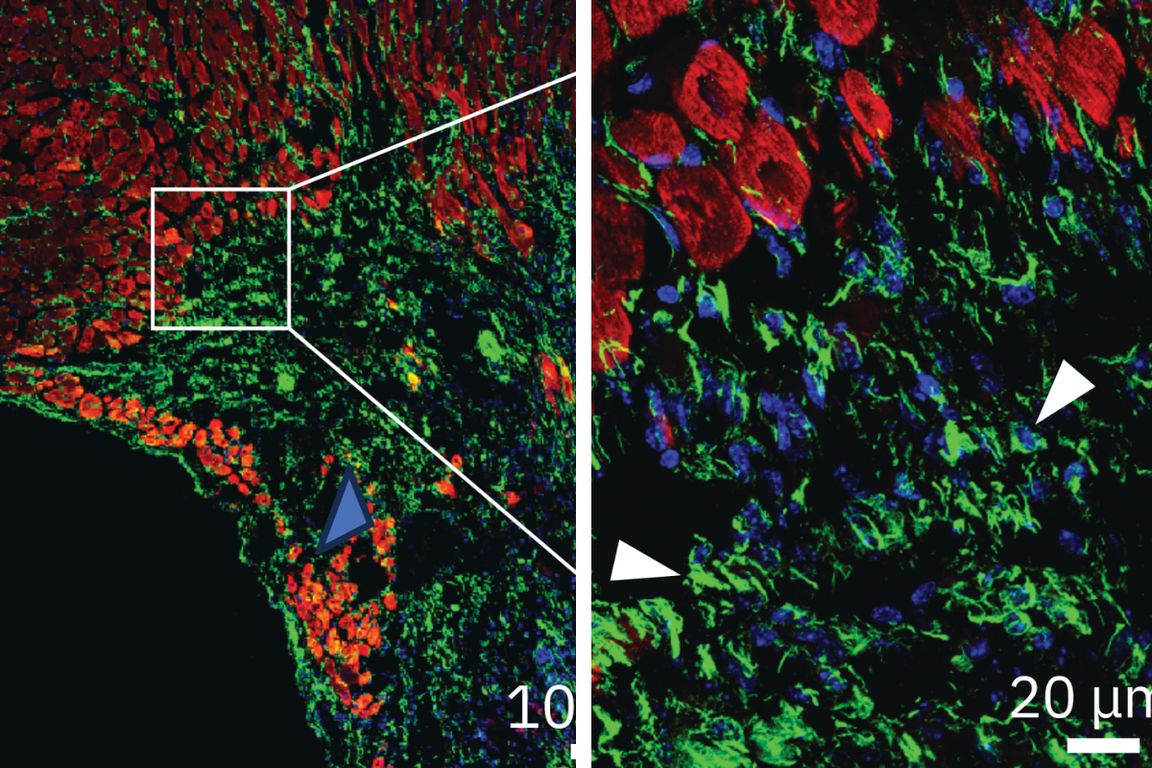

Solution #3: By mimicking zebrafish genetics, scientists induce heart re-growth in humans.

Martik discovered that humans carry many of the same genes as zebrafish, and these genes express themselves in similar ways while our hearts are first developing. But our versions of these genes don’t reactivate later in life in response to injury, unlike those of the zebrafish. Now, Martik is using CRISPR to tweak gene expressions in stem cell models of the human heart so they more closely mimic those of the zebrafish, with a goal of inducing our heart cells to regenerate.

Thanks to steady federal funding from the National Institutes of Health, Martik estimates therapies that induce human heart tissue to regenerate after a heart attack or other injury may be just a few years away.